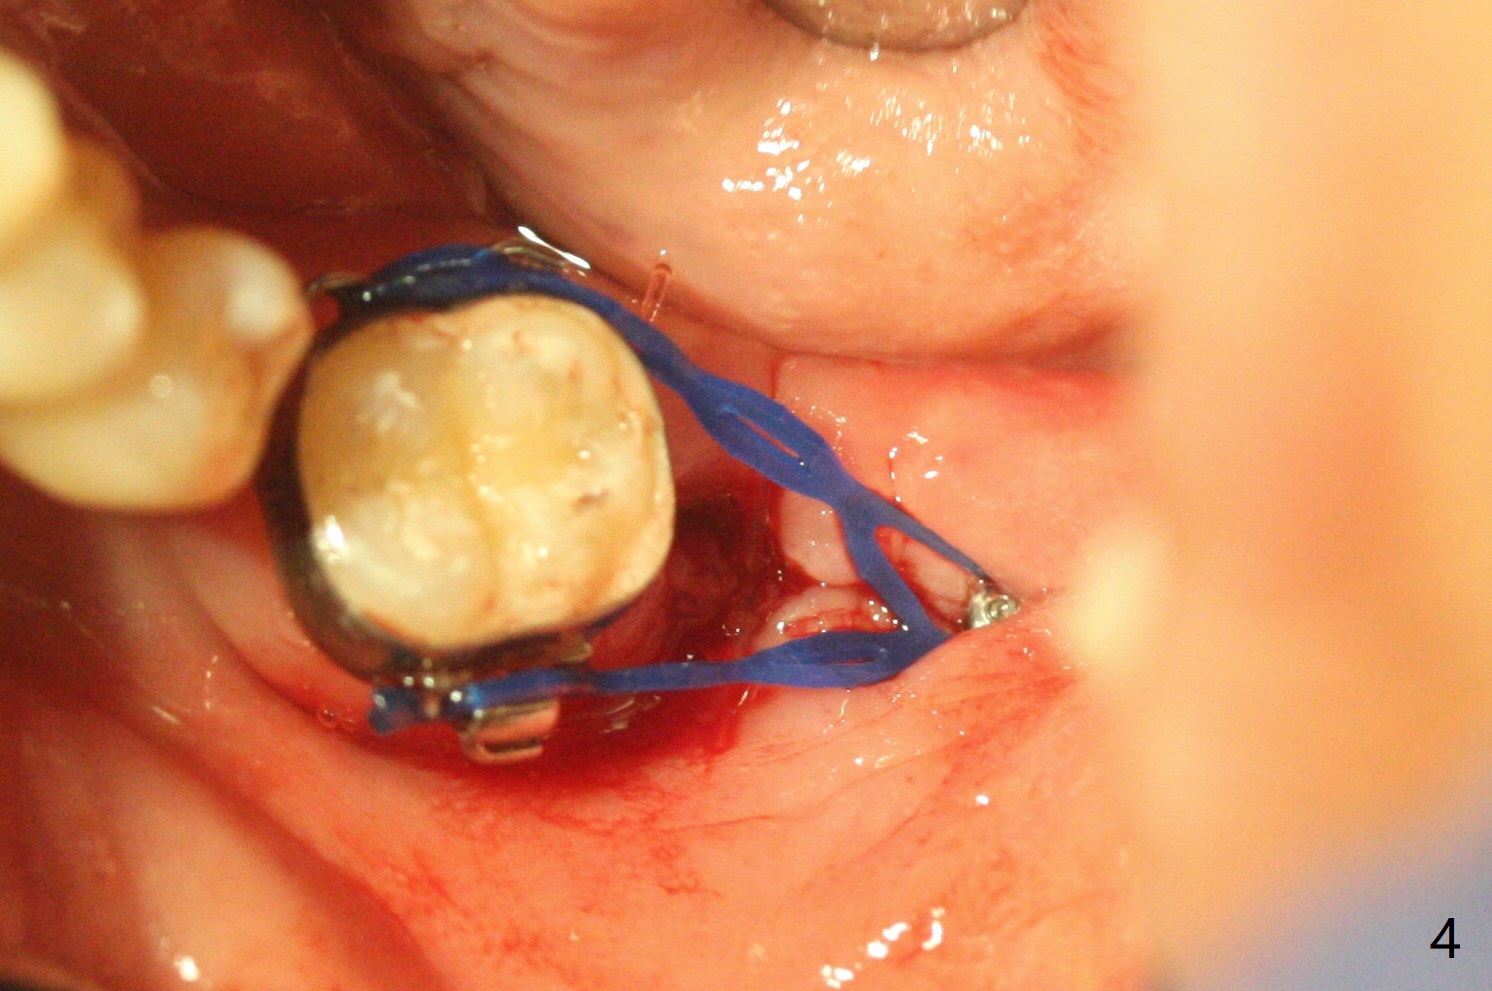

#17牙拔除植骨后1.5月(图一),准备在牙槽窝远中,即升支,种植一个抛锚,局麻下,首先不切开,钻洞,有些不放心,后来切开植入2x10(2)毫米一段式带球状基台植体(图二),植体根尖好像进入神经管(N)。CT显示植体却植入太接近舌侧骨板(图三:L),其实应该术前拍摄CT。由于18号牙同时扭转,安置磨牙圈(molar band),利用power chain进行牵拉以及矫正扭转(图四)。问题:升支抛锚种植位置对吗?power chain挂在抛锚上不稳定。